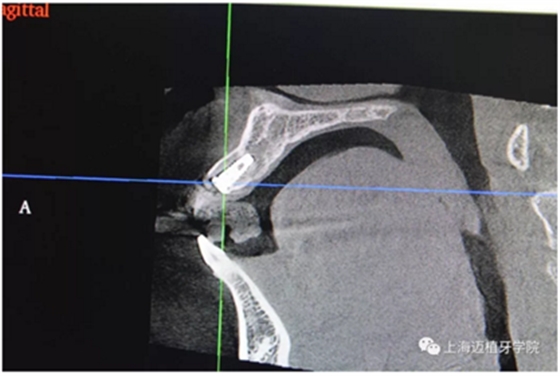

主訴:前門外傷牙根折要求修復(fù)?現(xiàn)病史:前門牙外傷,劈裂至根部,無法固定及其他修復(fù),要求種植?檢查:11牙冠2/3缺損,唇腭向劈裂,唇部紅腫。 CT示根折, 骨寬度9.47mm,距鼻底12.34mm,Ⅲ類骨。 口腔衛(wèi)生一般

術(shù)前全景片

CR片